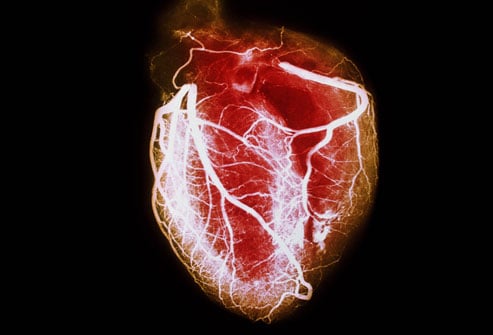

위에 서술한 방법들로 협심증으로 진단이 내려질 경우 카테터를 삽입하여 관상동맥 우회술이나 PCI가 필요한지 결정을 내리게 된다.

심폐기하/무펌프 관상동맥 우회술(CABG/OPCAB)의 경우 다양한 진단법을 통해 관상 동맥 혈관에 심각한 관련 질병이 보여 질 경우 시행하게 되는 수술 방법. 특히 좌관상동맥(left main) 혹은 3개 이상의 관상 동맥 관련(3-vessel) 질병이 관찰 될 경우, PCI 및 약물 치료 보다 훨씬 우월하며 환자의 생존률을 높히는 것으로 관찰 되었다. 또한 환자에게 당뇨나 심부전(S-CHF) 관련 질병이 보여질 경우 시행하기도 한다.